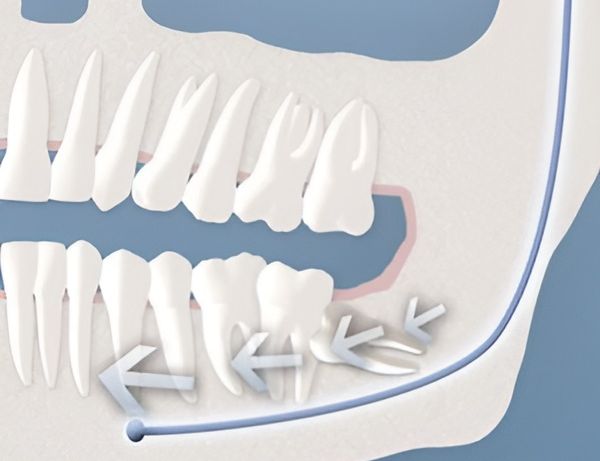

- Недостаточное пространство в челюсти

- Неправильное положение зуба

Важно понимать, что решение об удалении зуба мудрости принимается не только из-за боли или воспаления. Иногда зуб может находиться в «ретинированном» положении — то есть оставаться внутри десны или расти под углом. В таких случаях он не виден при обычном осмотре, и выявить проблему можно только с помощью рентгенографии. Именно поэтому регулярные профилактические визиты к стоматологу позволяют выявить скрытые риски и своевременно провести лечение.

Важно подчеркнуть, что не всегда требуется хирургическое удаление зуба мудрости — в некоторых случаях достаточно наблюдения. Если он правильно прорезался, не мешает соседним зубам и не вызывает воспаления, его можно оставить. Решение всегда принимается на основании клинической картины и рентгенографии. В моей практике около 30% пациентов сохраняют зубы мудрости под наблюдением, если они не представляют угрозы.